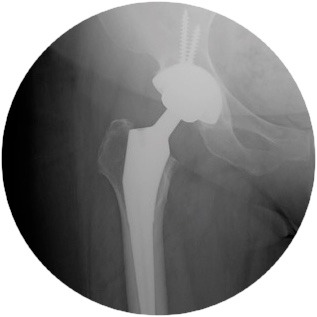

Hip Replacements:

Mr Pang has extensive experience in total hip replacements. He will discuss with you the differences in surgical techniques and types of prosthesis that will suit your needs.

He also has an interest in revision hip replacement surgery and is proficient in the use of megaprosthesis in more complex cases.